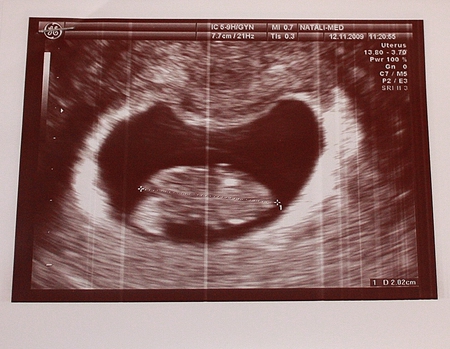

Вот такие мы были в самом начале:

По - тихоньку становимся похожи на человечка: